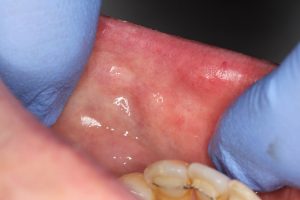

It is also excellent on all types of soft tissue. For example, irritating polyps can be removed with minimal fuss and excellent healing.